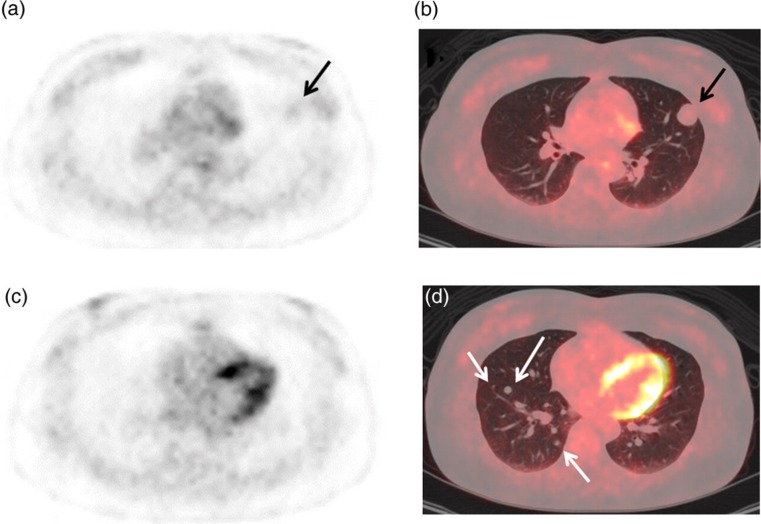

We report a case of multiple benign metastasizing leiomyoma (BML) lung nodules showing faint or non-avid uptake of F-18 fluorodeoxyglucose (FDG) (respective 1-hour early and 2-hour delayed maximum standardized uptake values; 1.3 or less and 1.2 or less) in a 50-year-old woman with a history of hysterectomy for uterine leiomyoma at the age of 38 years. When multiple lung nodules show faint or non-avid FDG uptake in a patient with a history of hysterectomy for uterine leiomyoma, BML should be included in the differential diagnosis.